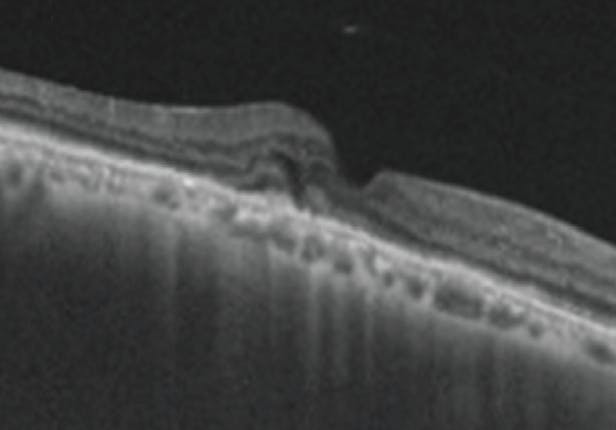

Given the persistence of SHRM on OCT, a combination therapy of IVZ and intravitreal triamcinolone acetonide 2 mg/0.05 mL (IVTA) was initiated.

At the 4-month follow-up, 1 month after the combination therapy, intraretinal fluid (IRF), SRF, and SHRM completely disappered and the patient was observed (Figure 6). At month 6, there was complete resolution of IRF, SRF, and SHRM with thinning of the fovea without any recurrence during this period or subfoveal scarring (Figure 7). OCTA of the right eye showed near resolution of the neovascular net. BCVA improved from 20/125 at baseline to 20/60 at month 6.

<p>Figure 6. One month after the patient received a combination of IVTA and IVZ, there was reduction of SHRM with no IRF/SRF.</p>

Figure 6. One month after the patient received a combination of IVTA and IVZ, there was reduction of SHRM with no IRF/SRF.

<p>Figure 7. The patient’s OCT shows complete resolution at month 6.</p>

Figure 7. The patient’s OCT shows complete resolution at month 6.